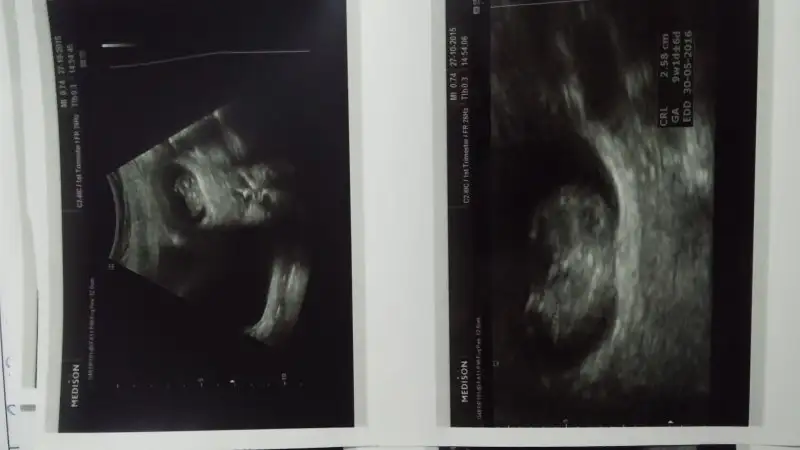

Kızlar bende 17 haftalık hamileyim dr önce kıza benziyor dedi sonra bir dra daha gittik o da kız dedi evelsi gün yine rutin druma gittik erkek bu bebek dedi kese 9 haftalık ultrason görüntüsünde eline alıp bakıldığında sağda ne düşüncem bilmiyorum :/

Bu 9 haftalık usgsi, dr bi öyle bi böyle söyleyince çok kafamız karıştı ne düşüncem bilemedim kız dediği için isim bile düşünmüştük elbise bile aldık :/